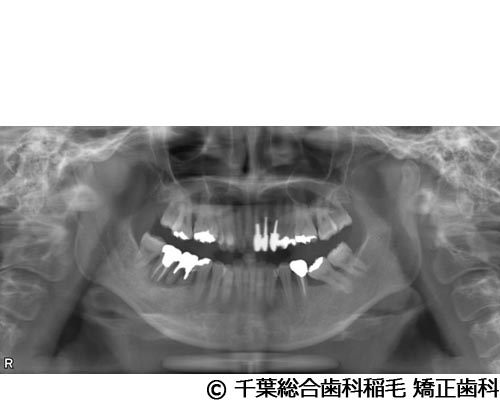

【症例3】上下5本インプラント埋入手術

- 治療前

- 治療後

- 治療名

- 上下5本インプラント埋入手術

- 費用

- 2,500,000円(税込)

- 期間

- 11ヵ月

治療内容

-

患者様の症状

欠損歯が多いため、お食事が取りにくく、インプラント治療のご相談でご来院されました。

治療法

状態の悪かった歯も含め、上下5本インプラントを埋入しました。

治療結果

奥歯でしっかり噛めるようになったと喜んでいただけました。

現在も定期健診で拝見させていただいています。

※治療結果は患者様によって個人差があります。